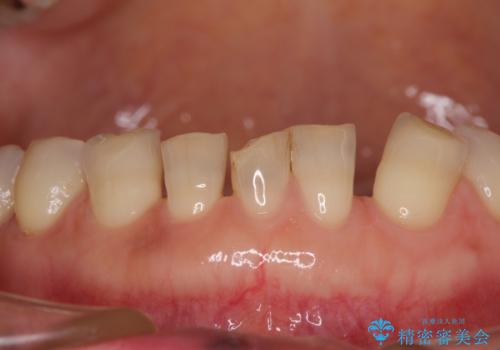

- 割れていると言われて放置してしまった歯や、前歯のデコボコなどが気になるとのことで来院された患者様です。

左上の歯は割れてしまっており、抜歯のうえインプラント治療が必要であり、他にも抜歯の必要な歯がある状態でした。

上顎はほぼ全ての歯をセラミッククラウンにて補綴治療を行う必要があるため、気になるデコボコや深い咬み合わせを改善するために下顎と上顎の臼歯部の矯正治療を行うこととしました。

過蓋咬合(下顎前歯が隠れてしまうほどの深い咬み合わせ)のため、スムーズに歯が動かず矯正治療に時間がかかりましたが、無事に仕上げることができました。